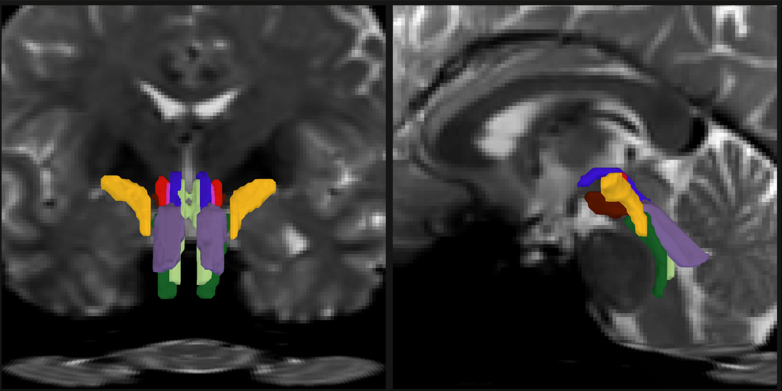

Researchers have developed a new way to resolve distinct bundles of nerve fibers in the brainstem. In this detail of a figure from the paper offering two different cross-section views of a human brain, individual bundles are segmented and color-coded.

Image: Mark Olchanyi/Emery Brown Lab